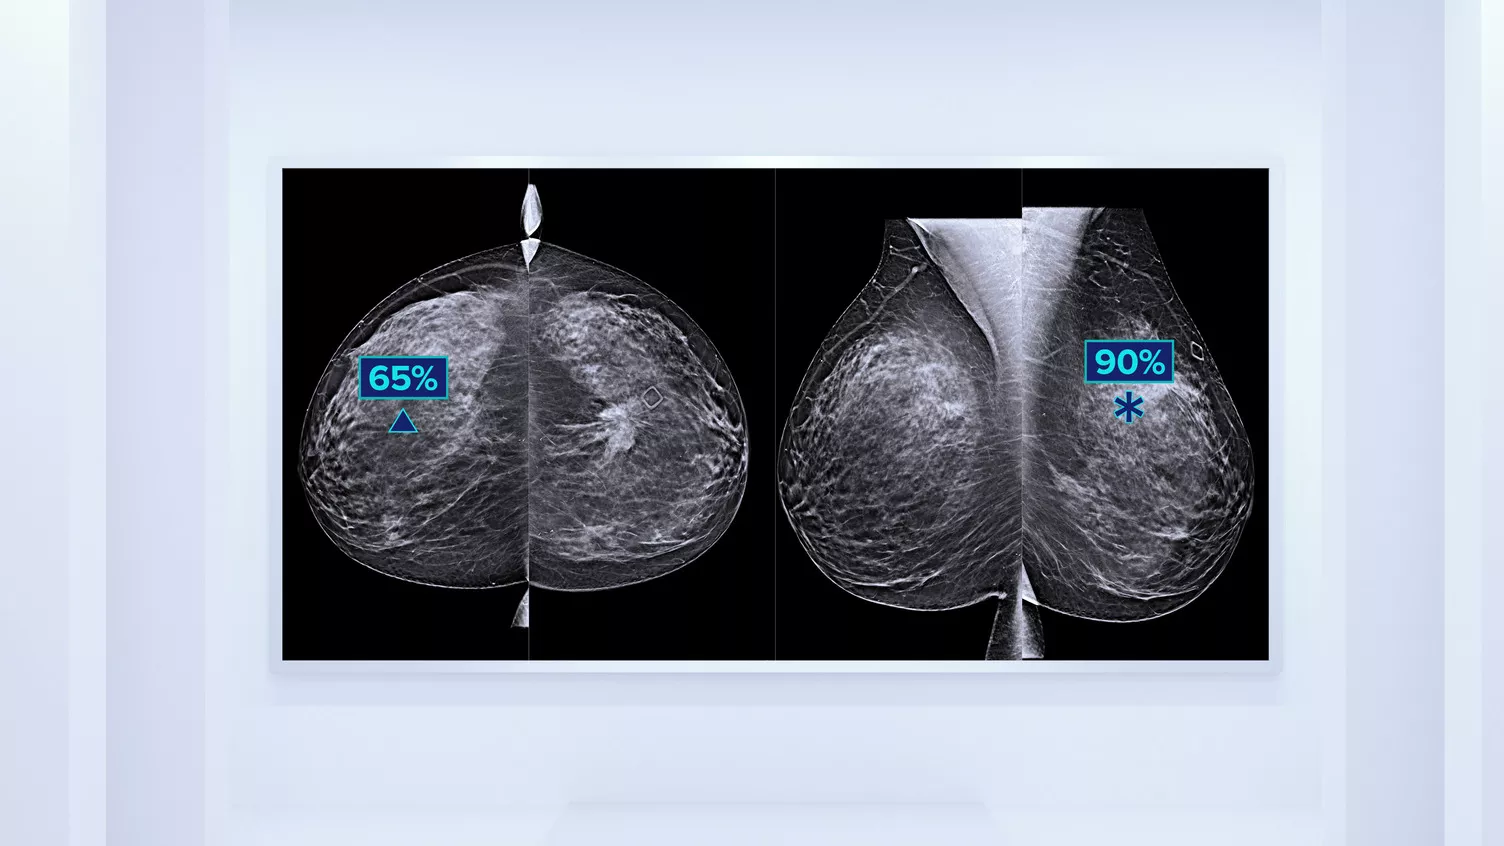

Higher breast density is known to increase a woman’s risk for breast cancer.1 The need for accurate, unbiased analysis is therefore critical. Powered by machine learning, Quantra technology software analyses both 2D™ and tomosynthesis images for distribution and texture of parenchymal tissue. It categorises breasts in four breast composition categories consistent with guidance from the American College of Radiology (ACR) BI-RADS Atlas 5th Edition.2

In addition to volume, pattern and texture of fibroglandular tissue may play just as an important role in mammographic cancer risk prediction.3-5 By analysing and categorising breast texture and pattern, our technology can deliver the accurate information you need to achieve more consistent and reliable scoring and confidently design patient-specific screening.

Objective machine learning algorithm that assigns breast density category based on analysis of breast tissue texture and patterns.

• Overcoming subjectivity in visual assessment, providing more consistent, and more reliable scoring.*

*Scores are based on ACR BI-RADS categories, in line with the revised guidance by the American College of Radiation (ACR) BI-RADS Atlas 5th Edition. This accounts for pattern and texture, compared with volume, when determining density.